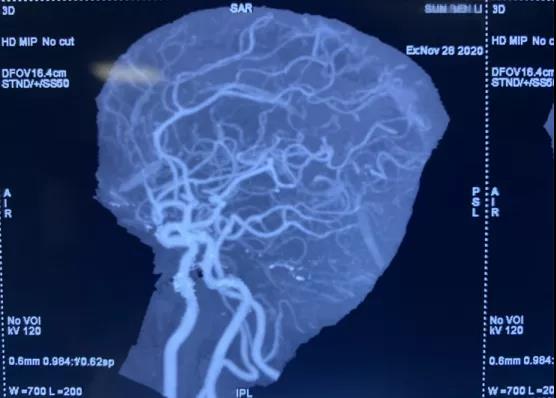

動(dòng)脈瘤診斷金標(biāo)準(zhǔn)為:數(shù)字減影血管造影(DSA) ,于學(xué)利主任親自把關(guān),盛國(guó)良、楊德森等神經(jīng)外科醫(yī)師立刻以頭部CTA為基礎(chǔ),急診行顱內(nèi)血管造影術(shù),術(shù)中明確了動(dòng)脈瘤的形態(tài)、大小、指向、周?chē)R近血管關(guān)系。